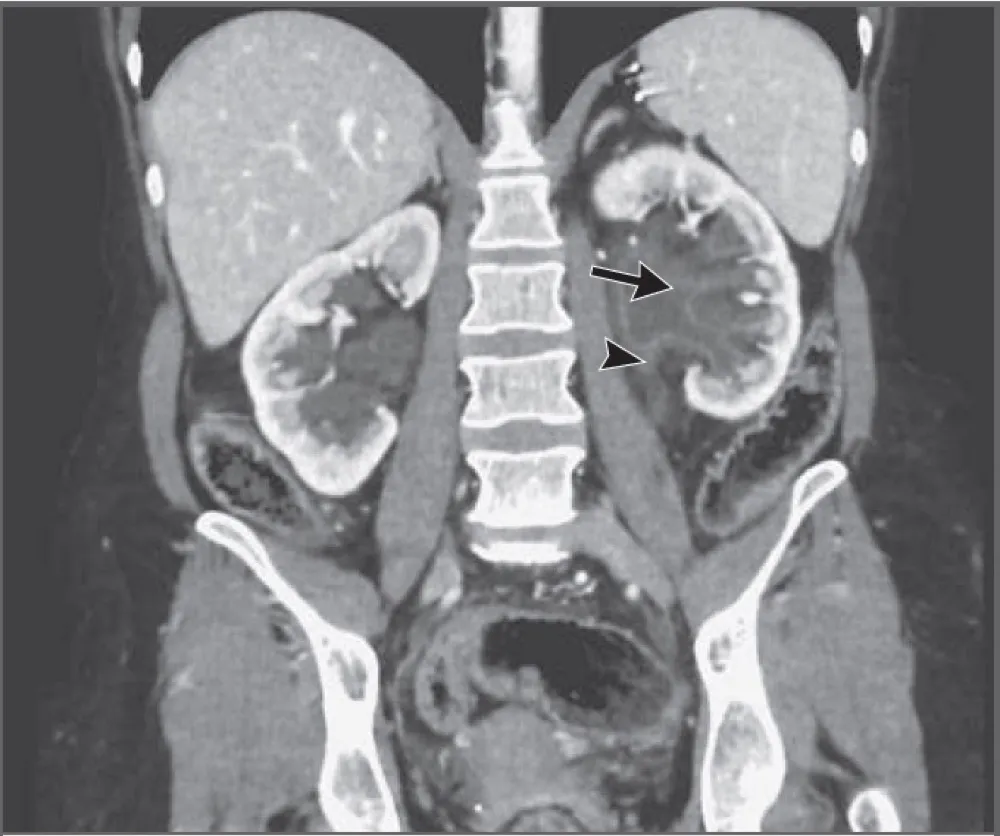

Uma causa incomum de hematúria glomerular intermitente!

Hematúria pós infecção, caso clínicos para auxiliar no entendimento de causas glomerulares comuns e raras...